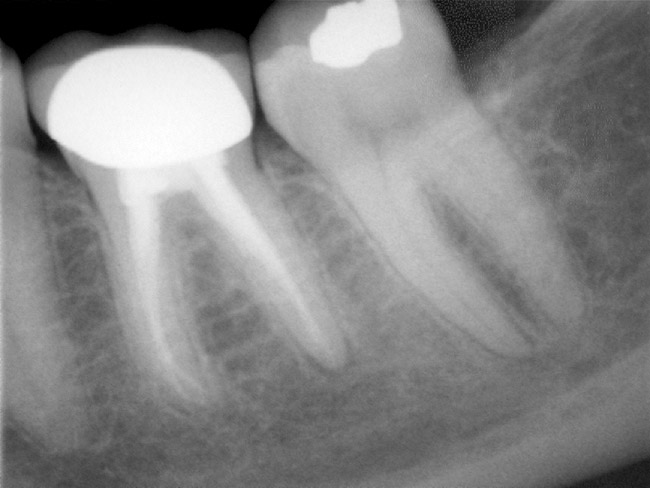

Figure 4a  Tooth No. 30 Nonsurgical root canal treatment had been completed 5 years before. The periapical radiograph revealed periradicular radiolucencies (periapical and in the furcation area).

Figure 4a

Figure 4b  The patient was asymptomatic, and periodontal probing depths were within normal limits; however, a new crown restoration was planned. Nonsurgical endodontic re-treatment was initiated. The intracoronal picture shows the previously treated 4 canals with infected gutta-percha filling.

Figure 4b

Figure 4c  Under high magnification, a furcation canal (Figure 4C) and a third distal canal (Figure 4D) were located.

Figure 4c

Figure 4d  Under high magnification, a furcation canal (Figure 4C) and a third distal canal (Figure 4D) were located.

Figure 4d

Figure 4e  The postoperative radiograph shows the re-treated tooth with 5 main canals.

Figure 4e

Figure 4f  The 1-year recall radiograph demonstrates the complete resolution of the periradicular radiolucencies.

Figure 4f